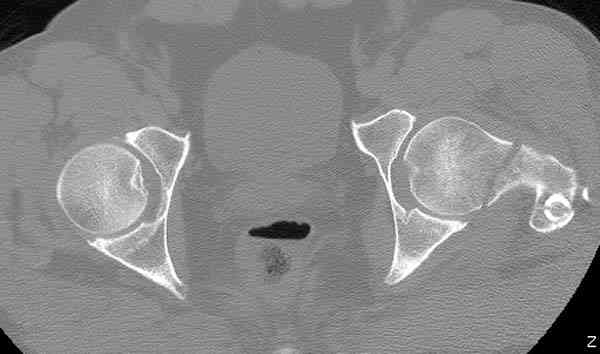

Здесь представлены снимки больного 65 лет, поступившего с диагнозом перелом

бедра после автоаварии.

В первый же день произведено антеградное штифтованием DePuy Trochanteric Nail.

На второй день (7) обнаружен пропущенный перелом,

сделаны Компьютерная Томограмма

и проведены шурурпы через и спереди штифта без удаления.